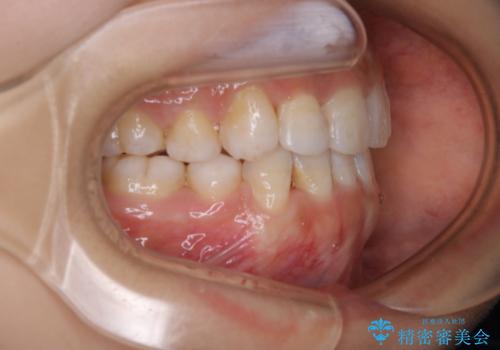

インビザライン単独での抜歯矯正治療

- 当院にてインビザライン治療を行っていた同僚の方からのご紹介でいらした方です。楽器を演奏されるとの事で、インビザラインによる矯正治療をご希望されました。治療の途中で一時的にワイヤー矯正に切り替える可能性もあることもご了承頂いた上で治療を行いました。

1日20時間以上、正しくインビザラインを使用して頂いたおかげで、ワイヤーに切り替えることなく矯正治療を終了することが出来ました。抜歯症例でしたが比較的短期間で見た目が劇的に改善し、大変喜んでいただけました。